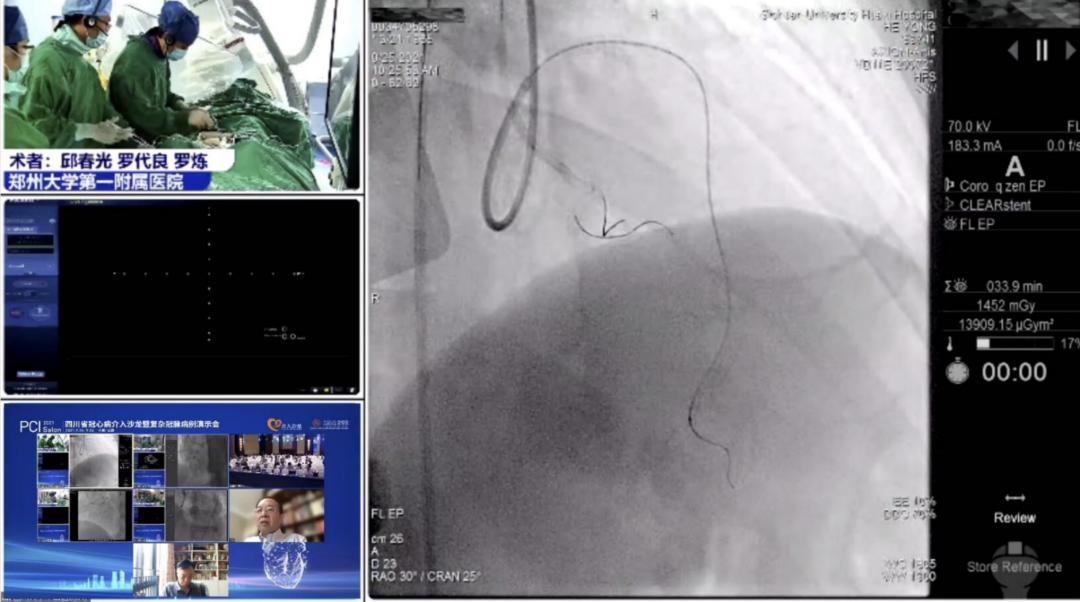

9月25日,大会隆重开幕,大会执行主席、四川大学华西医院贺勇教授主持,大会创始人及名誉主席、四川大学华西医院心内科黄德嘉教授,北京力生心血管健康基金会管廷瑞理事长,大会主席、四川大学华西医院陈茂教授,大会创始人及名誉主席东莞康华医院贾国良教授等多位专家领导分别以线上、线下参会形式共同出席开幕式,并为大会开幕致辞。随后,来自全国多地的冠脉领域资深术者通力配合,带来了11场极具难度和技巧的复杂冠脉病例手术演示及微课讲座。同期进行的护理及技术人员论坛、冠脉腔内影像与生理学论坛、冠心病诊疗论坛、降脂治疗论坛&心衰药物进展论坛、血栓抽吸、药物球囊、愈合型支架等专题学术内容应接不暇、精彩纷呈。